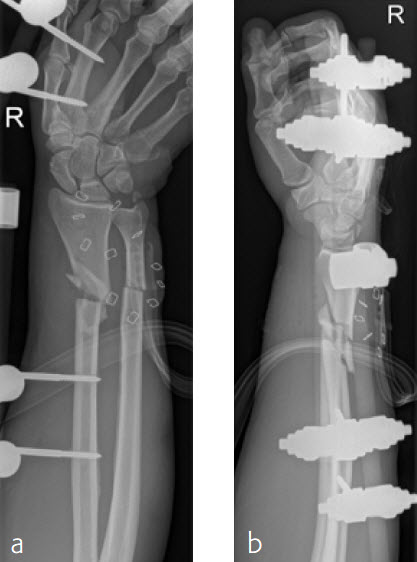

A 59-year-old farmer suffered a crush injury with an open forearm fracture (AO22 C2, Gustilo and Anderson IIIB) (Fig 5). Initial stabilization was carried out by external fixator (Fig 6). After four rounds of debridement and capillary ingrowth of a splitting skin graft at day 17, the VA LCP Extra Long Two-Column plate was used for fixation of the radius. A 2.7 mm LCP Condylar Plate was used for fixation of the ulna. The plates provided good stability for a functional after-treatment.

At the 3-month follow-up, the patient was full weight bearing with healing fractures (Fig 7).